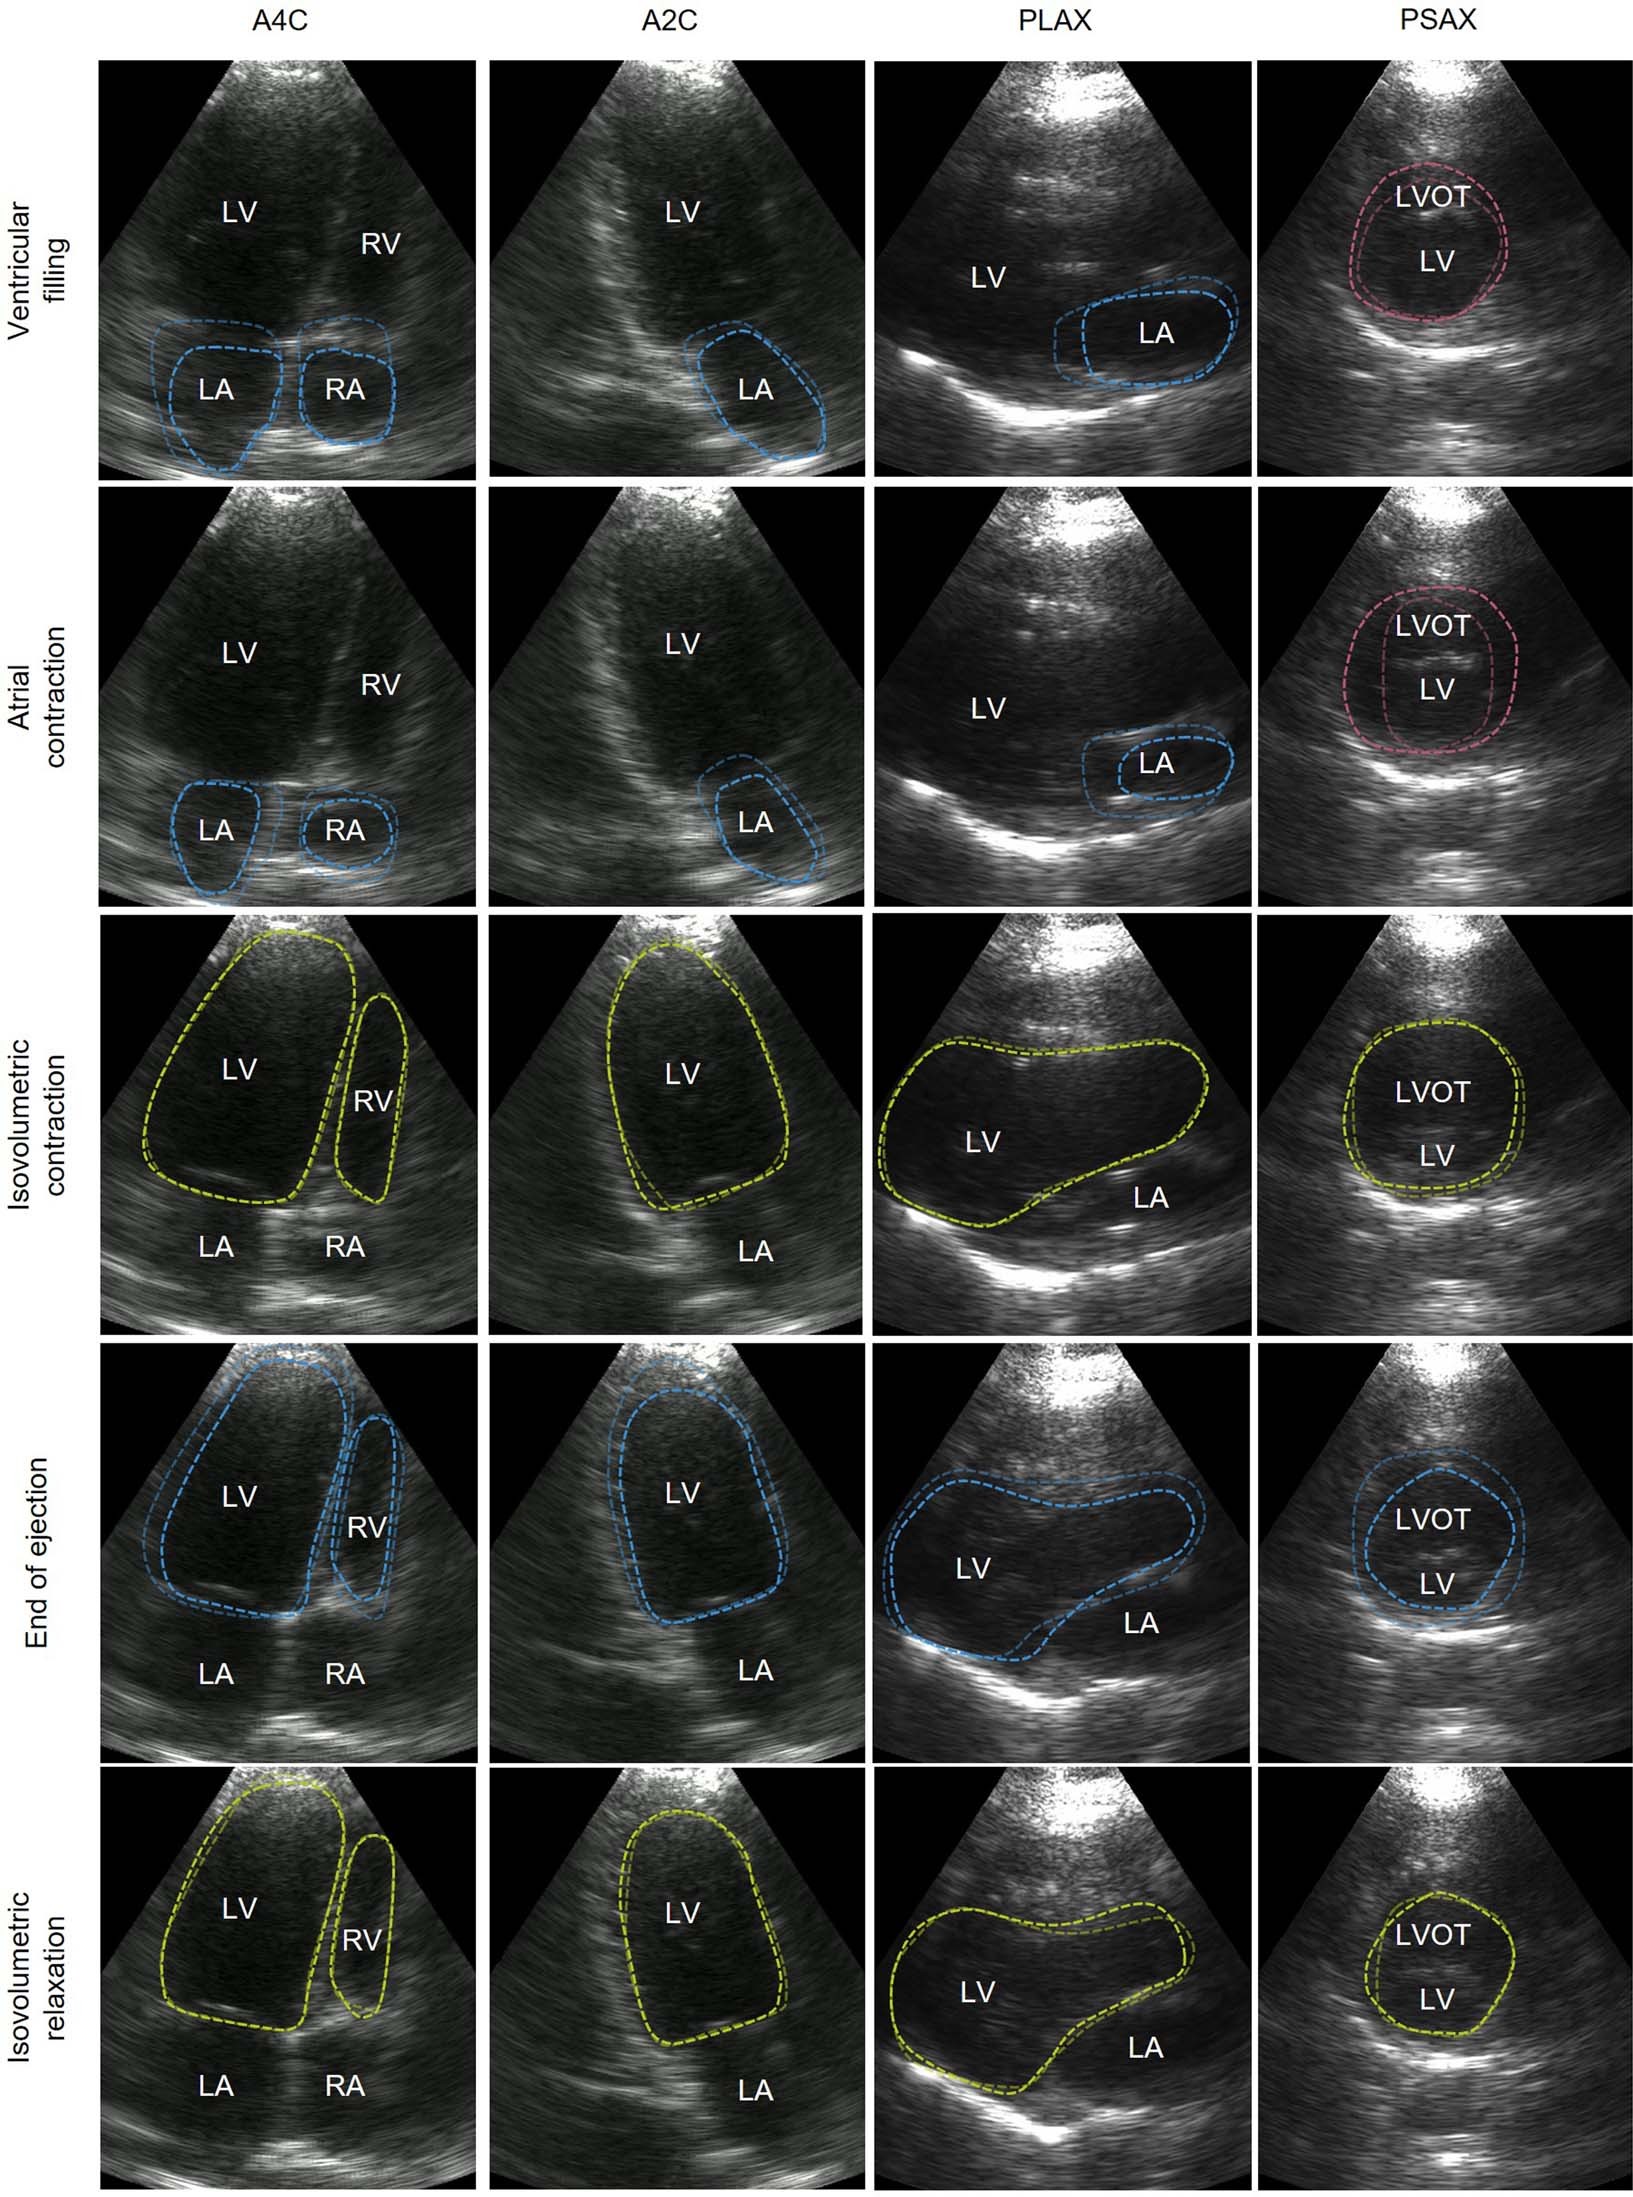

Extended Data Fig. 8: Different phases in a cardiac cycle obtained from B-mode imaging.

The rows are B-mode images of A4C, A2C, PLAX and PSAX views in the same phase. The columns are B-mode images of the same view during ventricular filling, atrial contraction, isovolumetric contraction, end of ejection and isovolumetric relaxation. The dashed lines highlight the main features of the current phase. Bluish lines mean shrinking in the volume of the labelled chamber. Reddish lines mean expansion in the volume of the labelled chamber. Yellowish lines mean retention in the volume of the labelled chamber. A2C, apical two-chamber view; A4C, apical four-chamber view; LA, left atrium; LV, left ventricle; LVOT, left ventricular outflow tract; RA, right atrium; RV, right ventricle; PLAX, parasternal long-axis view; PSAX: parasternal short-axis view.